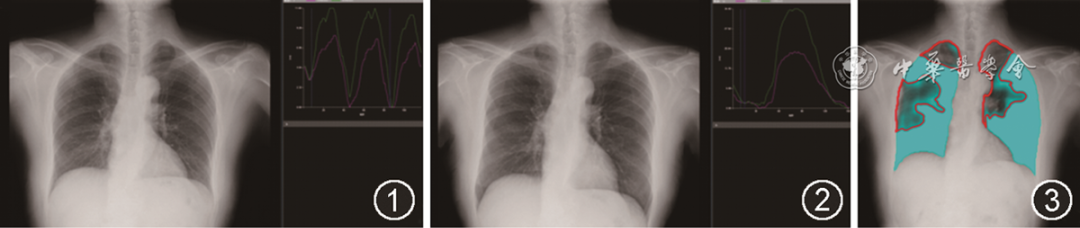

入院体检:生命体征平稳,双肺呼吸音清晰,未闻及干湿性啰音,无胸膜摩擦音,心腹未见异常,双下肢无浮肿。改良呼吸困难指数(modified Medical Research Council,mMRC):4级。入院动脉血气分析:pH值为7.428,PaO2为93.75 mmHg(1 mmHg=0.133 kPa),PaCO2为32.93 mmHg,HCO3-为21.40 mmol/L,OI为446 mmHg;MYO为73.38 μg/L,CK-MBm为2.41 μg/L,CK为133 U/L,CRP为2.12 mg/L。血常规、肝功能、肾功能、血电解质、甲状腺功能、凝血功能、D-二聚体、肿瘤标志物、真菌D葡聚糖、痰培养、心肌酶谱、Pro-BNP、自身抗体全套等检验结果未见明显异常。肺通气功能、弥散功能基本正常(VC 3.88L,FVC 3.88L,FEV1 3.09 L,FEV1占预计值%:130.4%,FEV1/FVC:79.68%)。FENO为13 ppb。X线胸片未见异常。肺动脉CTA(CT pulmonary angiogram,CTPA)未见肺动脉栓塞,可见右肺下叶后基底段少许慢性炎症表现。动态X线胸片(Dynamic Chest Radiography,DCR)检查提示膈肌移动度低于正常值(2023年2月21日平静呼吸膈肌移动度,右侧为8.40 mm,左侧为11.60 mm;尽力呼吸膈肌移动度,右侧为19.60 m m,左侧为34.40 mm),通气情况差(双肺灰色区域占双肺的39%),见图1, 2, 3。

图1 例1患者动态X线胸片(2023年2月21日)可见平静呼吸膈肌移动度右侧为8.40 mm,左侧为11.60 mm

图2 例1患者动态X线胸片(2023年2月21日)可见尽力呼吸膈肌移动度右侧为19.60 mm,左侧为34.40 mm

图3 例1患者动态X线胸片(2023年2月21日)可见肺通气显像双肺灰色区域占双肺的39%